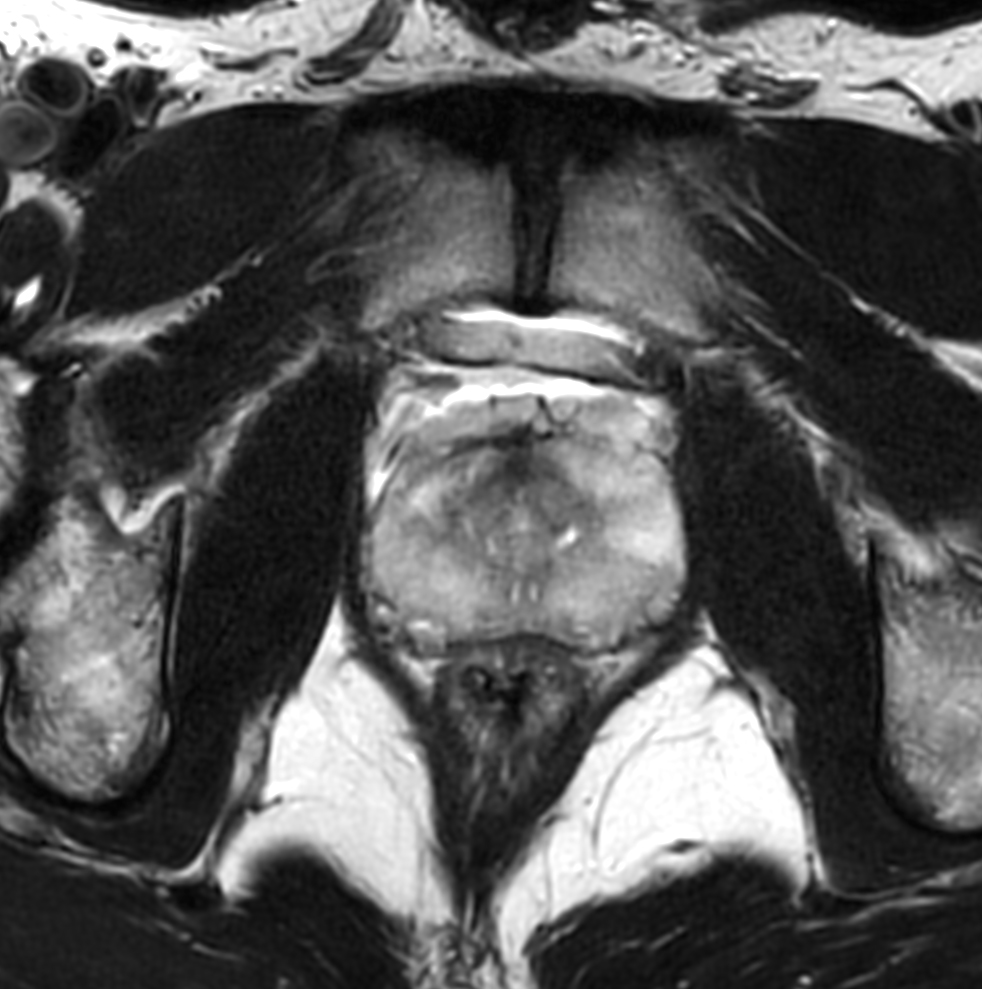

Prostate with dS ZOOM imaging

Aarhus University Hospital, Denmark

Used Solution

• System

• Coil

• Clinical Application